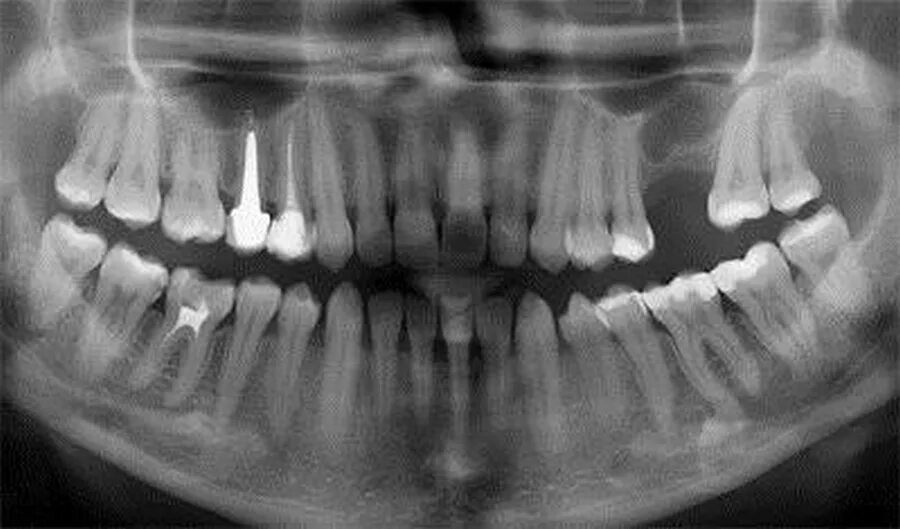

Киста зуба что это